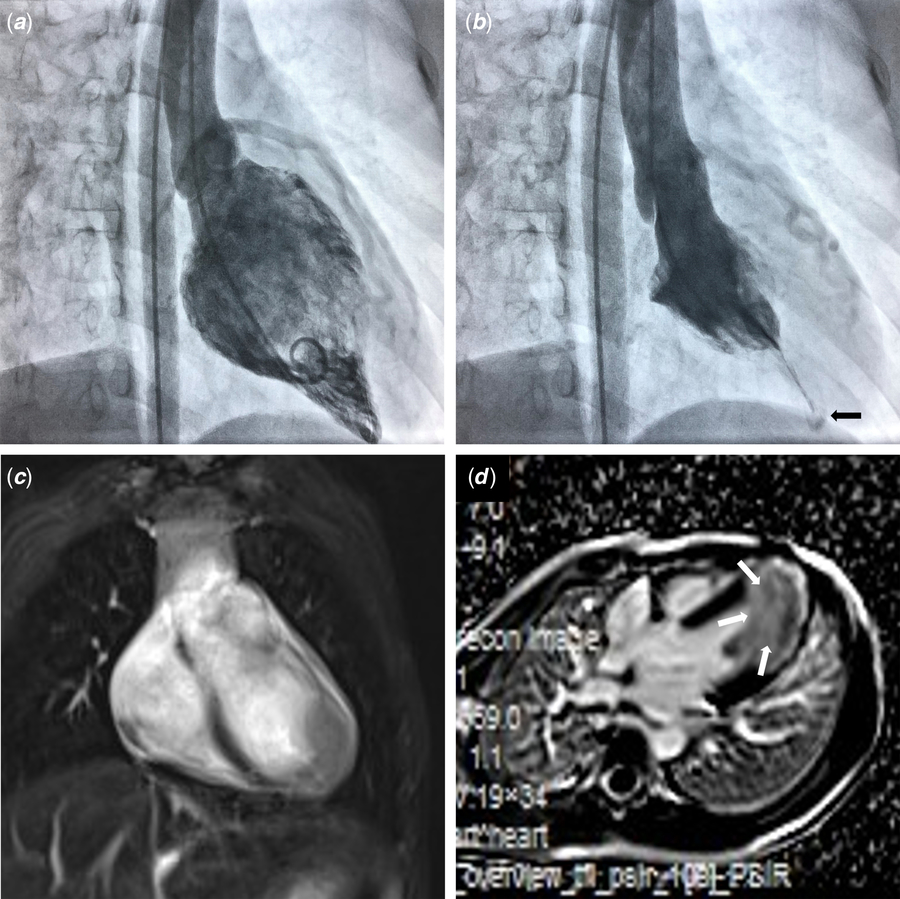

From www.cambridge.org

Apical hypertrophic cardiomyopathy an cause of exertional Exertional Chest Pain In Young Athletes Noncardiac causes for chest pain,. •exercise testing in athletes can be utilised to: Chest pain, both at rest and during exercise, is a common reason for cahap to seek medical attention. Assess & improve cardiopulmonary fitness evaluation of athletes with cardiac symptoms. The devastating impact of even relatively infrequent sudden deaths in young athletes offers justification for restriction from competition. Exertional Chest Pain In Young Athletes.